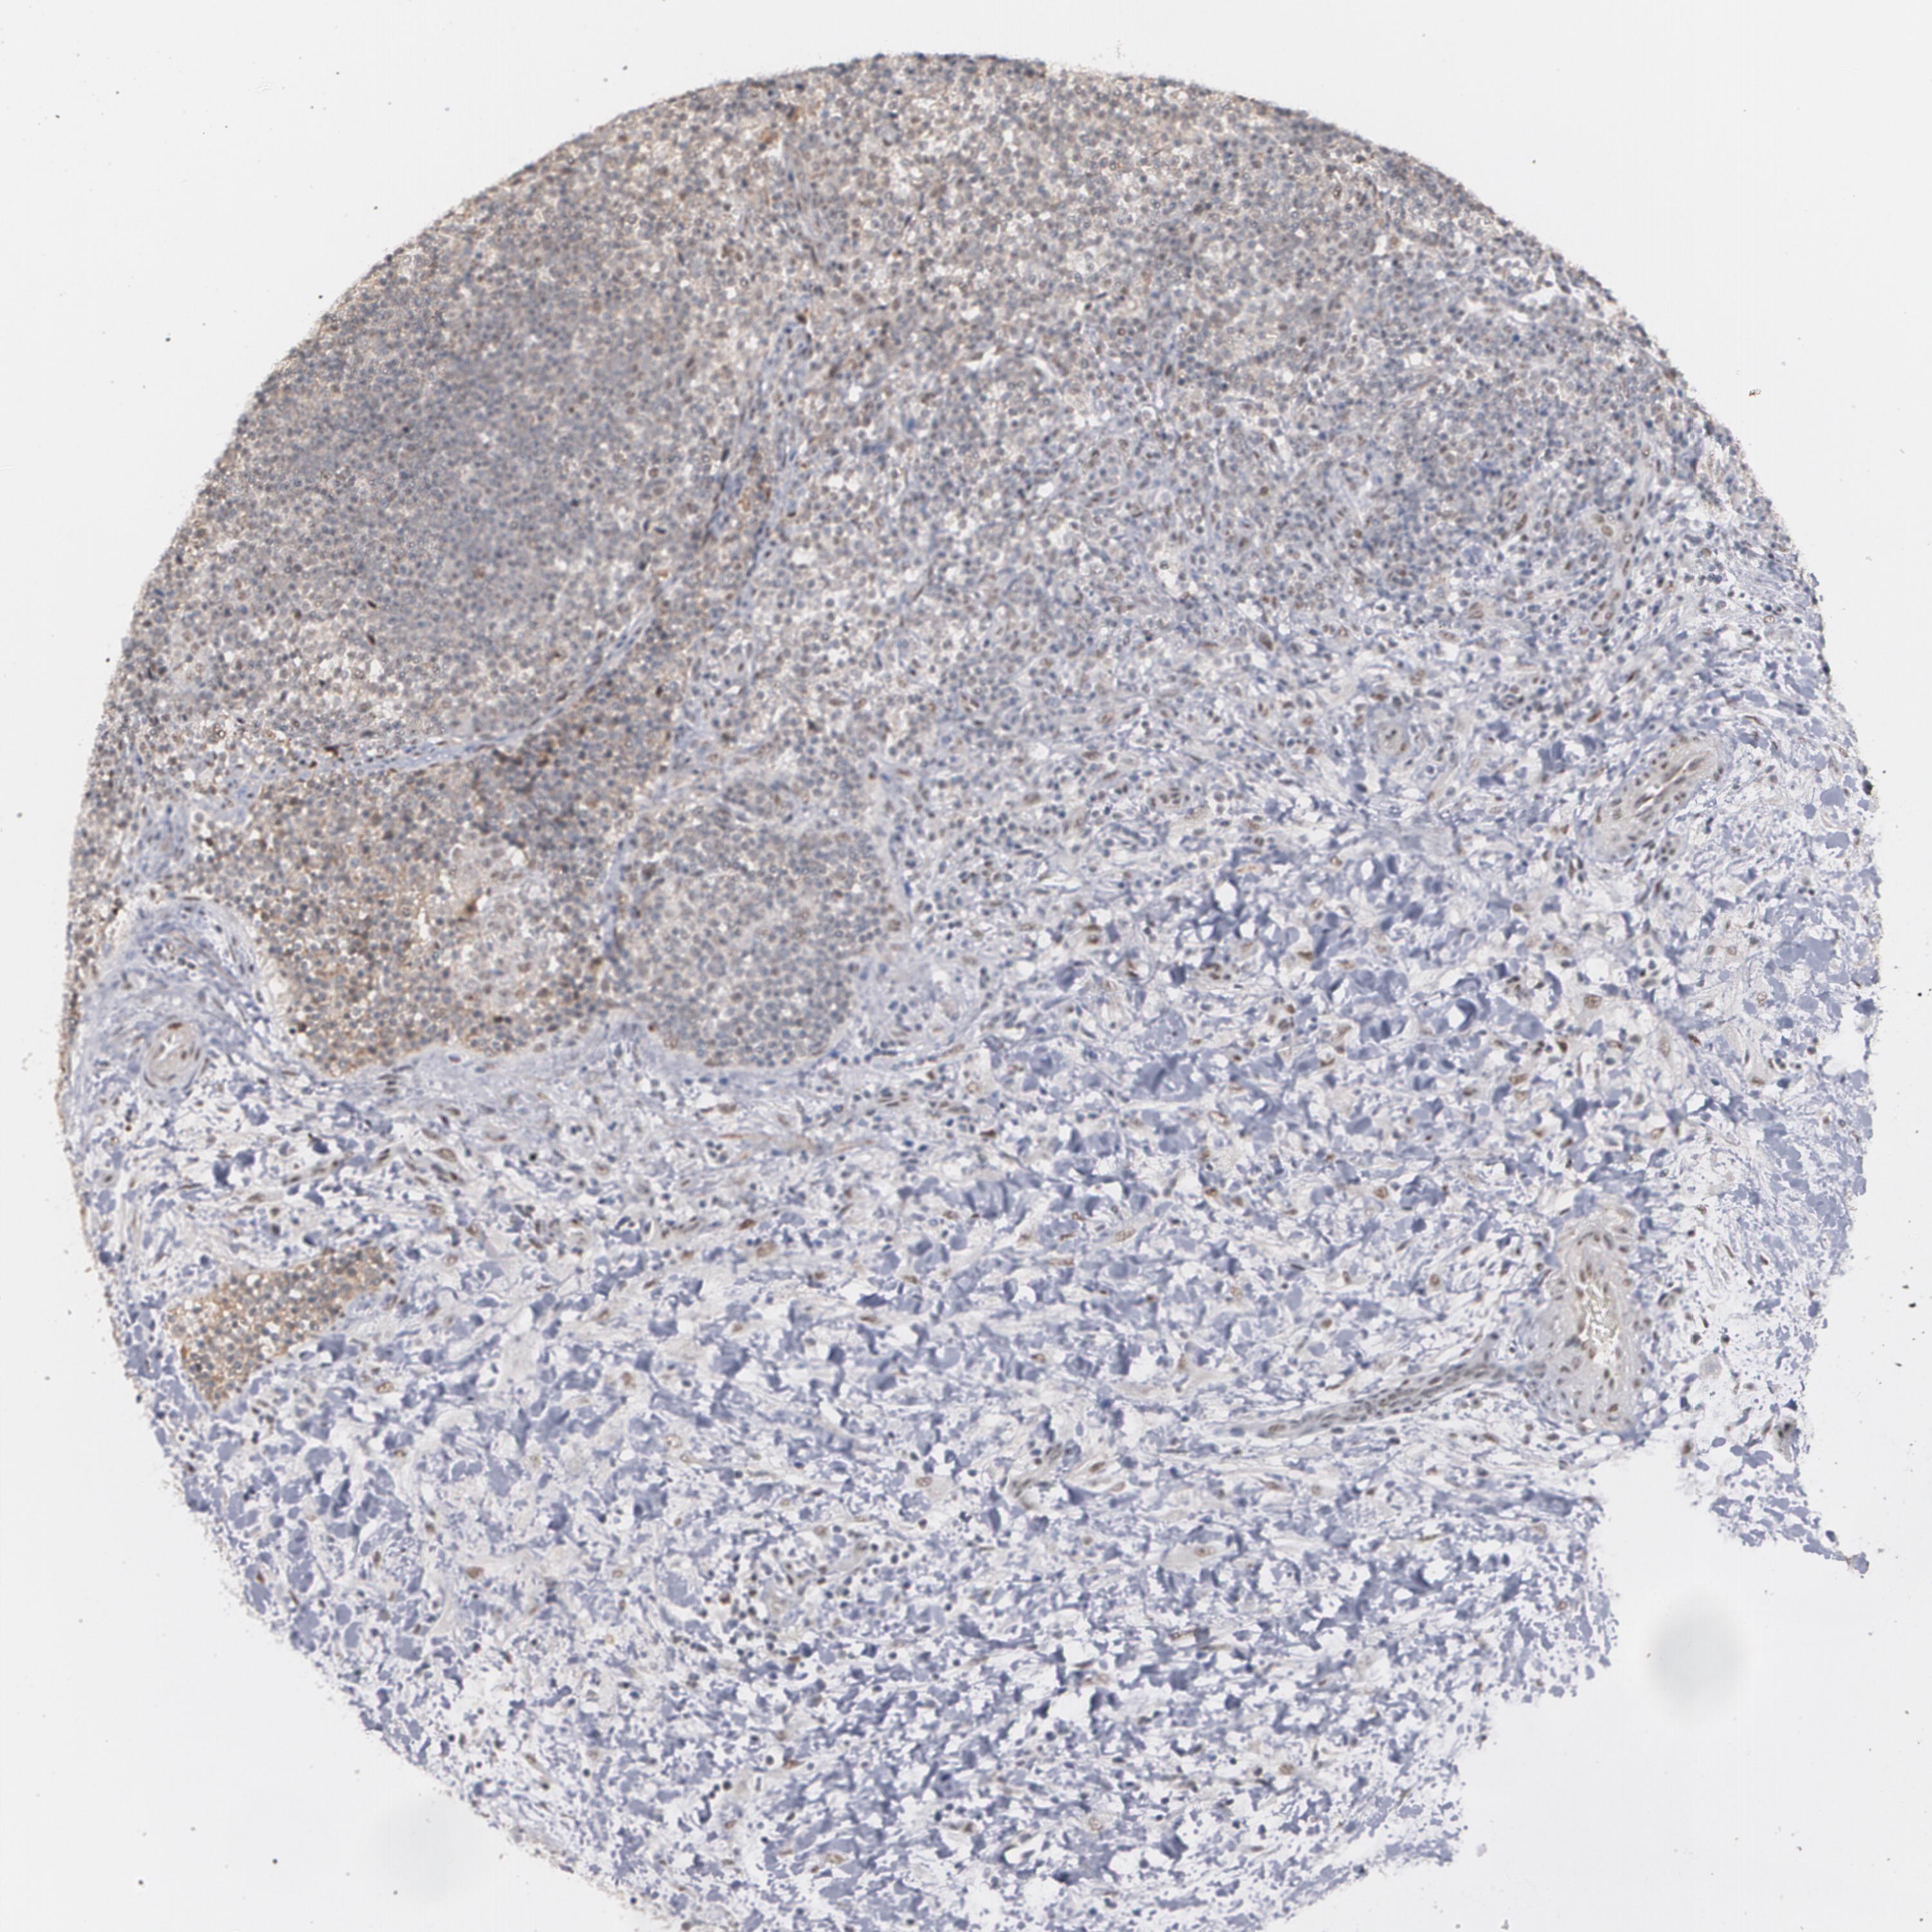

CANCER LYMPHOMA Show tissue menu

LYMPHOMA - Protein expressioni

A mouse-over function shows sample information and annotation data. Click on an image to view it in a full screen mode. Samples can be filtered based on level of antibody staining by selecting one or several of the following categories: high, medium, low and not detected. The assay and annotation is described here.

Antibody stainingi

Antibody staining in the annotated cell types in the current human tissue is reported as not detected, low, medium, or high, based on conventional immunohistochemistry profiling in selected tissues. This score is based on the combination of the staining intensity and fraction of stained cells.

Each image is clickable and will lead to virtual microscopy that enables deeper exploration of all samples and also displays staining intensity scores, fraction scores and subcellular localization as well as patient and tissue information for each sample.

Antibody HPA001664

Staining

High

Medium

Low

Not detected

Intensity

Strong

Moderate

Weak

Negative

Quantity

>75%

75%-25%

<25%

None

Location

Nuclear

Cytoplasmic/membranous

Cytoplasmic/membranous,nuclear

Malignant lymphoma, non-Hodgkin's type, High grade

Malignant lymphoma, non-Hodgkin's type, Low grade

Hodgkin's disease, NOS